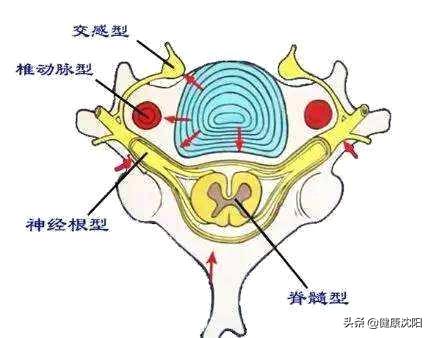

颈椎病主要分为四型:

1.神经根型颈椎病

2.脊髓型颈椎病

3.椎动脉型颈椎病

4.交感神经型颈椎病